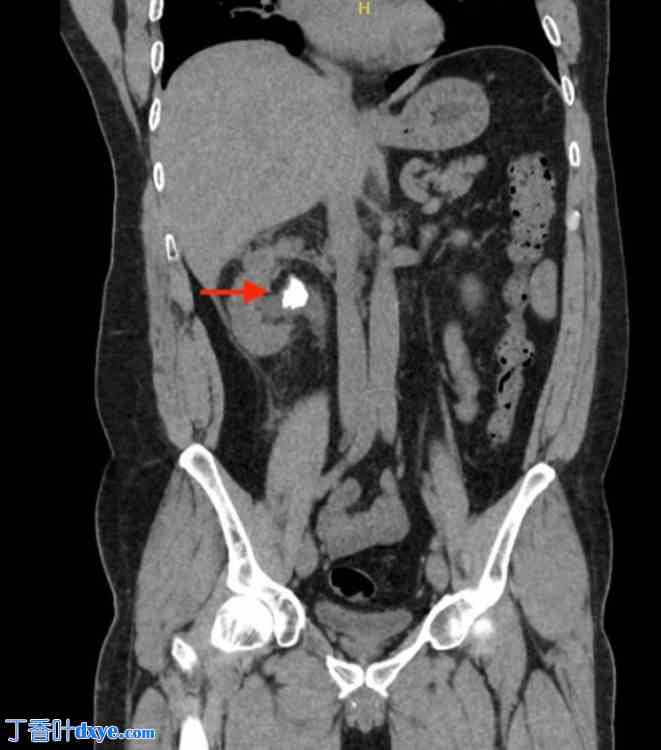

一名43岁男性患者因右肾绞痛和发热入院。非增强CT扫描显示肾盂内有一枚2.5厘米的梗阻性结石(图1)。患者接受了静脉抗生素治疗,介入放射科医生在中肾盏内插入了一根导尿管,引流出脓性分泌物。三周后,一位经验丰富的泌尿内镜医师利用预先建立的导尿管通道,行俯卧位经皮肾镜取石术(PCNL)。术中,首先将一根Roadrunner PC亲水导丝(Cook Medical)经导尿管送入中肾盏,试图将导丝穿过嵌顿结石(图2)。随后取出导尿管。接着,将一根Kumpe 5 Fr通路导管(Cook Medical)沿导丝置入,旨在引导其到达近端输尿管。透视下经Kumpe导管注射造影剂,可见一粗大的管状结构,造影剂迅速向上排出(图3)。在进行增强透视检查后,确认Kumpe导管尖端位于下腔静脉腔内(图4)。随即召开紧急多学科会诊,包括泌尿内镜医师、血管外科医师、介入放射科医师和麻醉医师。患者血流动力学稳定,无活动性出血或呼吸压力升高的迹象。在注射造影剂的同时,小心地将Kumpe导管回撤至肾中盏,未发生经导管进入肾单位或腹膜后间隙的出血。随后,介入放射科医师通过新建立的通道将8 Fr NT导管插入肾上盏。术中患者血流动力学稳定。术后静脉注射造影剂的CT扫描未见造影剂晕染或出血迹象。之后,患者成功接受了经皮肾镜取石术(PCNL),从肾上盏取出结石。

图 1.

腹部 CT 扫描冠状位图像显示右肾盂内有一枚 2 厘米的结石。